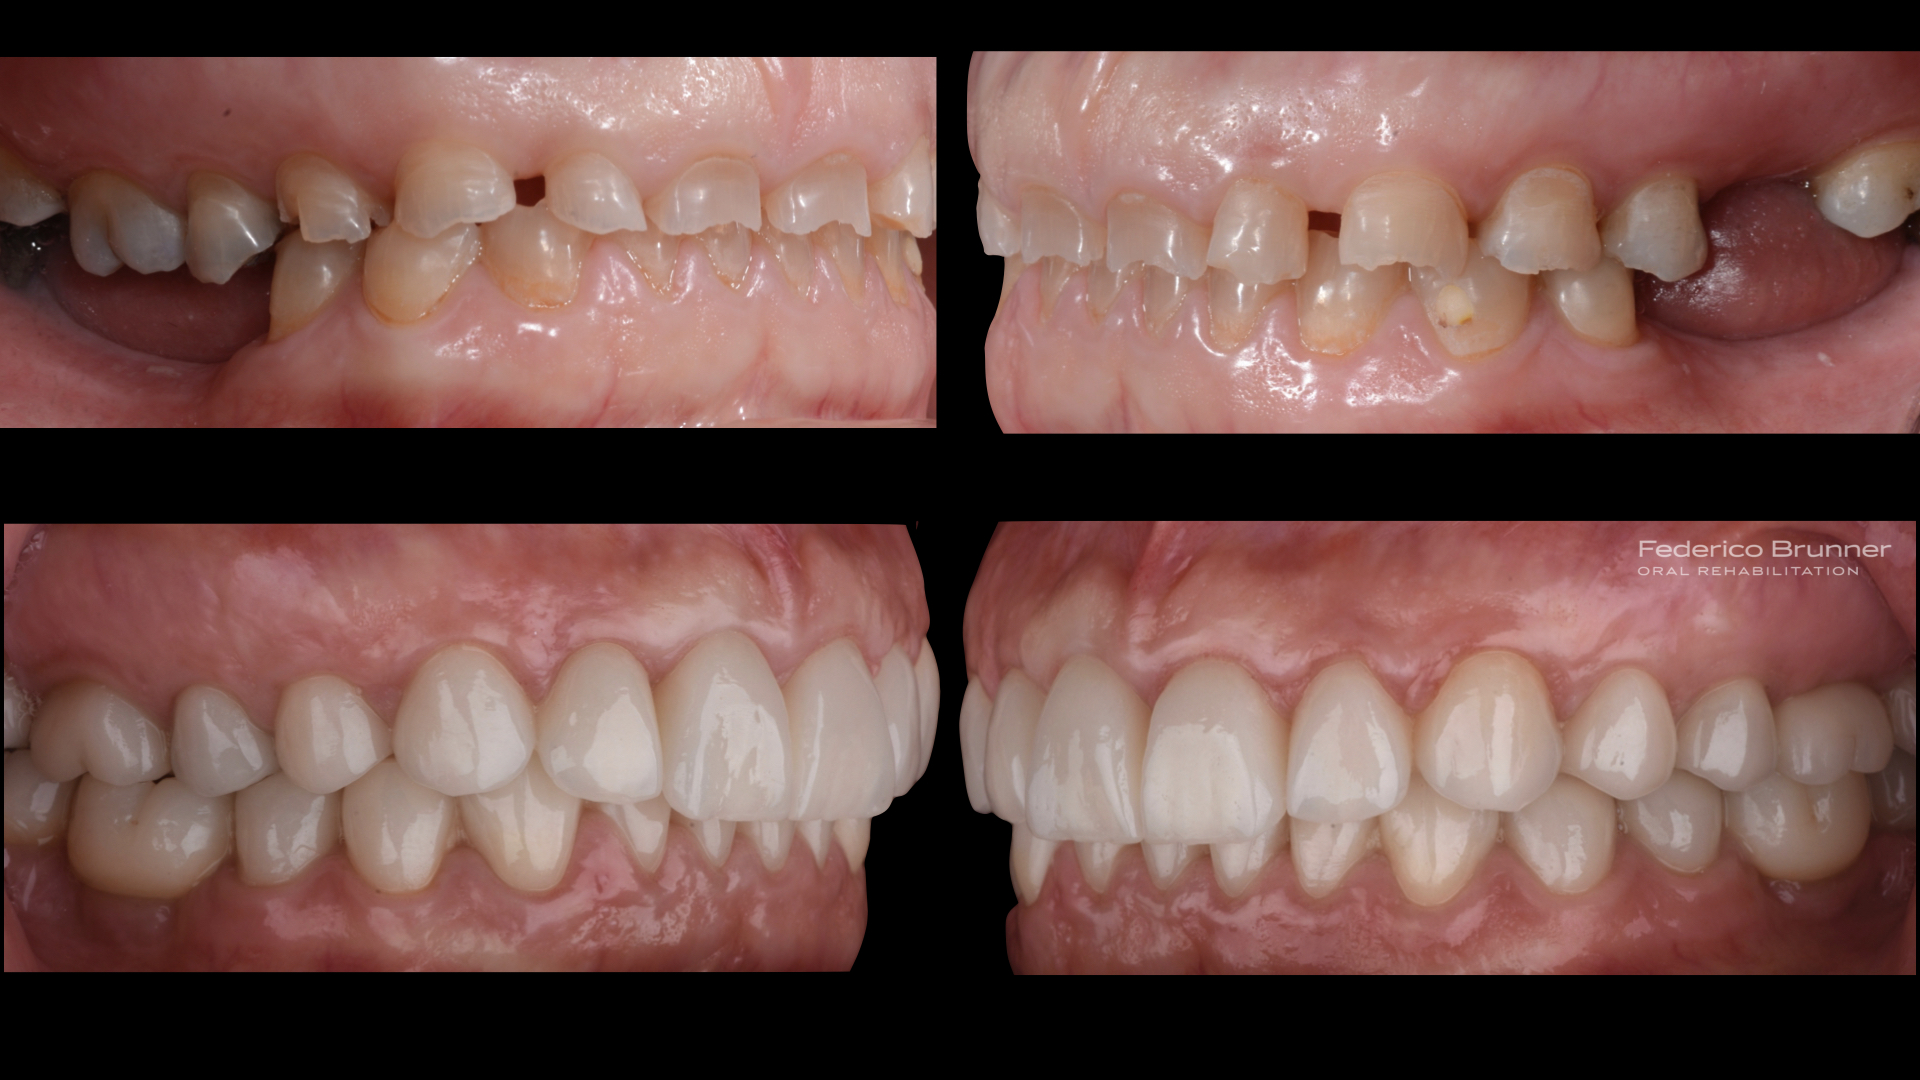

Una vez concluido el estudio de la sonrisa, creamos una simulación real o "mock-up" para que la paciente pudiera visualizar y comprender el resultado final antes de iniciar el tratamiento.

La paciente quedó encantada con el "mock-up", lo que nos permitió comenzar el tratamiento. En este proceso, realizamos un alargamiento coronario para mejorar la sonrisa gingival, ya que exponía demasiada encía. Luego, planificamos y ejecutamos una rehabilitación total cerámica adherida sin metal. Además, reemplazamos las piezas perdidas con implantes dentales, lo que nos permitió restaurar la función y hacer desaparecer los problemas masticatorios y digestivos.

Con la recuperación de la estética, la paciente recuperó su alegría y volvió a sonreír con confianza.